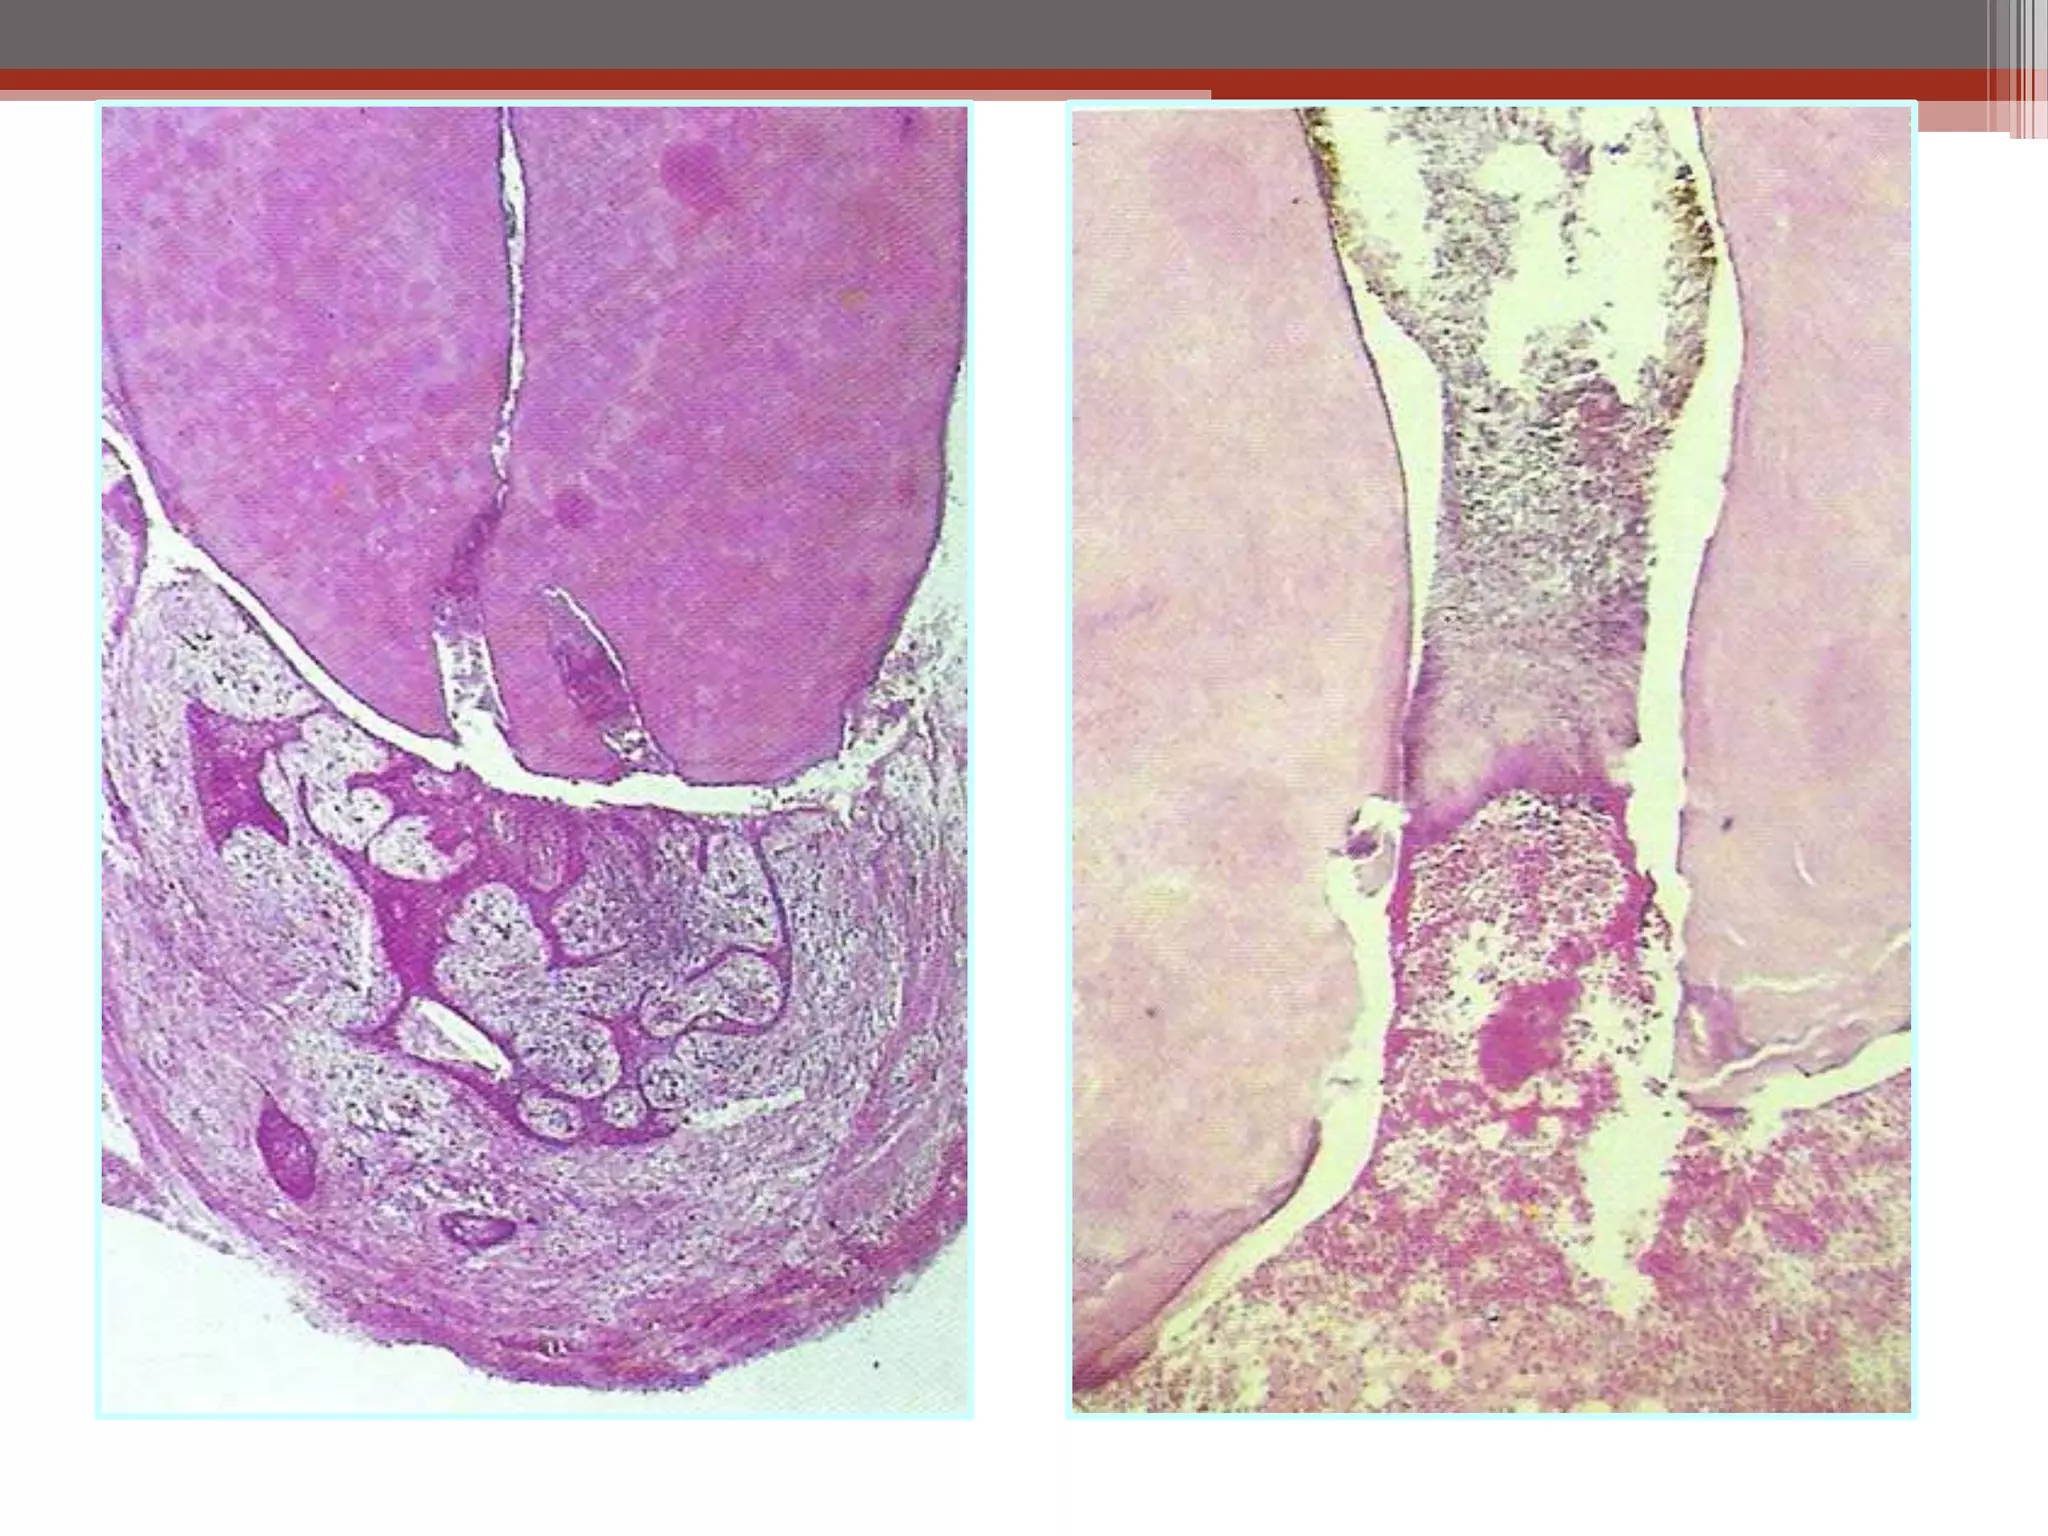

Chronic Hyperplastic Pulpitis

Histopathological Features:

• The polyp consists of granulation tissue.

• It contains delicate connective tissue, fibers and blood vessels.

• Mononuclear inflammatory cell infiltration.

• The polyp is covered with SS epithelium.

• Treatment: RCT or extraction of the tooth.

Chronic Hyperplastic Pulpitis Etiology: ClinicalFeatures: • Opened cavity. • Red pinkish soft nodule protruding • Starts as chronic or into the cavity. acute. • Almost in children and young adults. • Wide apical foramen • Relatively insensitive to manipulation. [Children]. • Most common in deciduous molars. • Must be differentiate from gingival polyp. Histopathological Features: • The polyp consists of granulation tissue. • It contains delicate connective tissue, fibers and blood vessels. • Mononuclear inflammatory cell infiltration. • The polyp is covered with SS epithelium. • Treatment: RCT or extraction of the tooth.